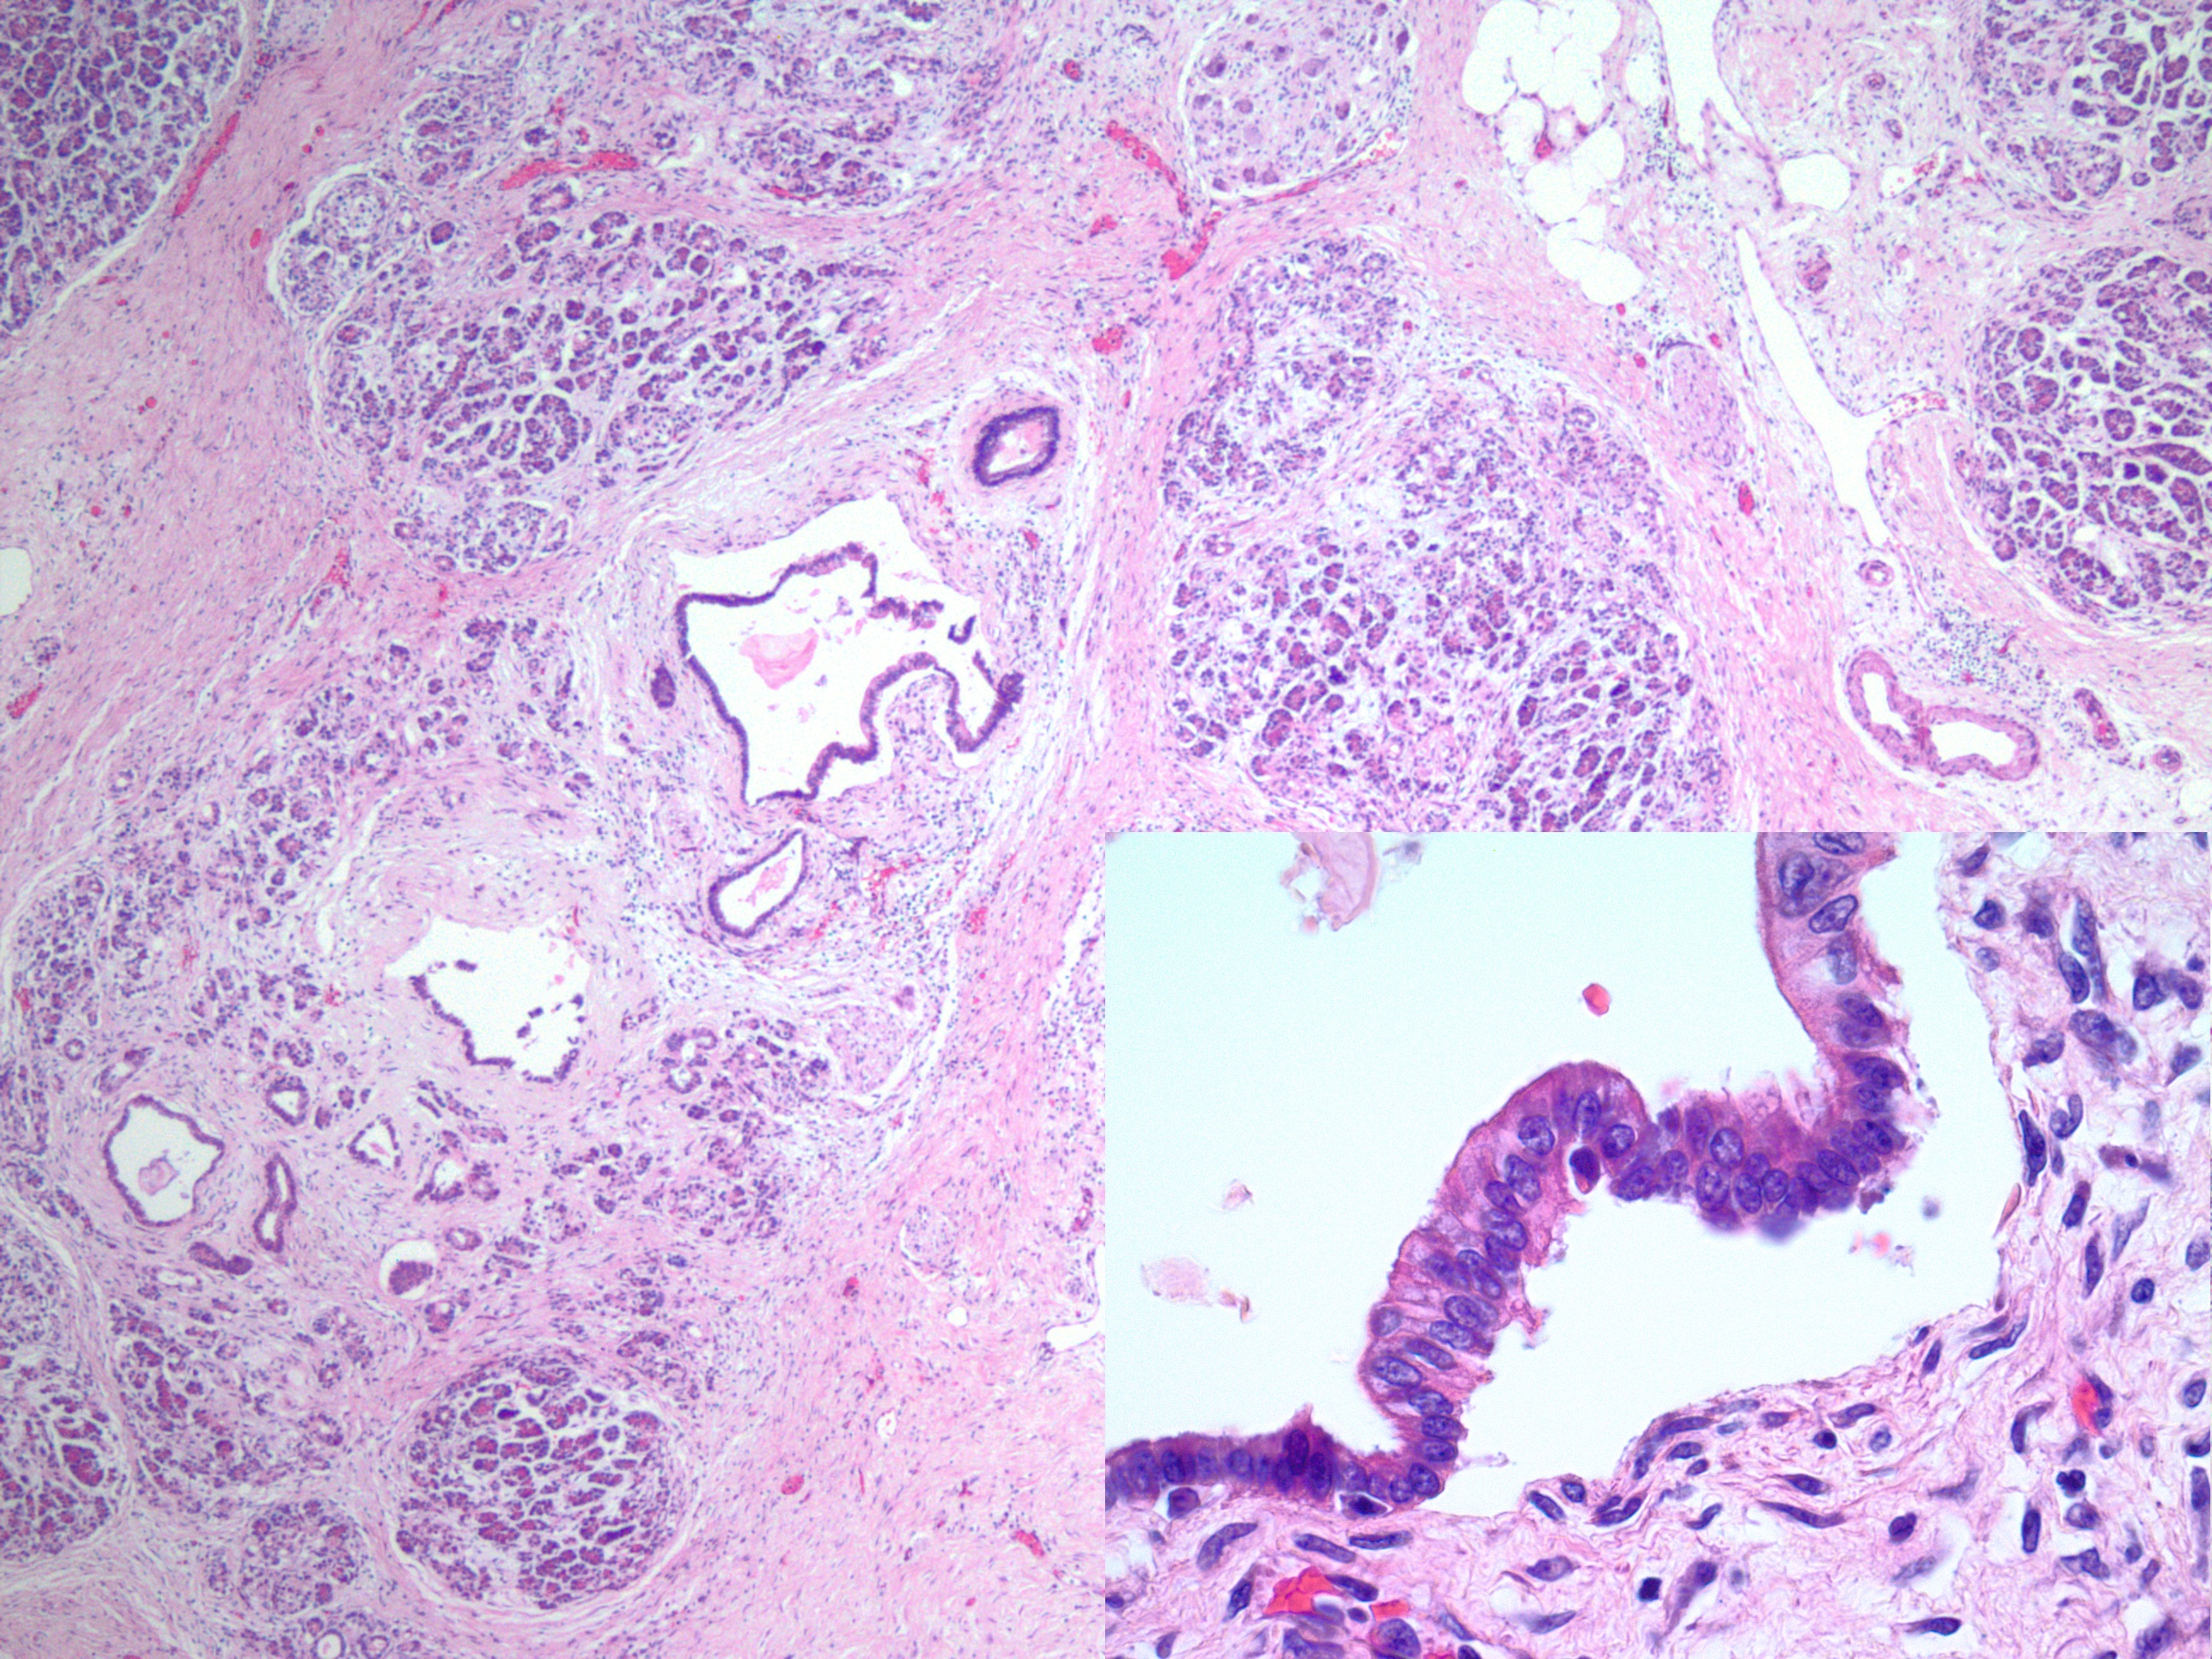

Cytologic Diagnosis: Positive for Malignancy, Adenocarcinoma

Biopsy/Pathologic Diagnosis: Corresponding Surgical Pathology H&E Slides of Core Biopsy of 4R Lymph Node, Positive for Malignancy, Adenocarcinoma with malignant cells staining positive for TTF-1 and negative for GATA3 and SOX10. PD-L1 immunohistochemical staining is positive.

Differential Diagnosis:

Given the patient’s prior clinical history of breast cancer, metastatic breast adenocarcinoma was an important differential diagnosis to consider. Cytologically, metastatic breast adenocarcinoma can present with cohesive clusters of epithelial cells, enlarged nuclei, and prominent nucleoli, which may overlap with the appearance of lung adenocarcinoma.9 Because these tumors may share similar glandular morphology, IHC staining is often necessary to determine the primary site. Breast adenocarcinoma typically demonstrates positivity for markers such as estrogen receptor (ER), progesterone receptor (PR), GATA3, and mammaglobin.9

Metastatic melanoma was also an important consideration given the patient’s history. Melanoma may show pleomorphic cells with prominent nucleoli, abundant cytoplasm, and variable cellular cohesion, which can sometimes resemble poorly differentiated carcinoma on cytologic preparations.10 Because melanoma demonstrates wide morphologic variability, immunohistochemical stains are essential for diagnosis. Melanoma typically shows positivity for markers including S100, SOX10, HMB-45, and Melan-A, which help distinguish it from epithelial malignancies.10